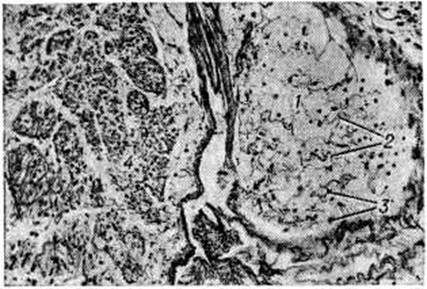

Воспалительную инфильтрацию, по их мнению, следует рассматривать как реактивный процесс на первичные изменения в миелиновой оболочке. Миелинотоксические факторы вызывают разрушение миелина в органотипических культурах ткани периферической нервной системы и имеют диагностическое значение. Эта модель используется для изучения иммунологический реакций замедленного и немедленного типа в развитии экспериментального аллергического Полиневрит Введение животным в инкубационном периоде заболевания ряда препаратов (АКТГ, циклофосфамида, антилимфоцитарной сыворотки) подавляет развитие процесса. Лечебный действием обладает невритогенный основной белок миелина, используемый в смеси с неполным стимулятором Фрейнда. Патологическая анатомия. В патоморфологические отношении Полиневрит разделяют на паренхиматозные и интерстициальные. Среди паренхиматозных Полиневрит различают формы с преимущественным изменением миелина и леммоцитов (периаксональные Полиневрит) и формы с преобладанием поражения аксона (аксональные Полиневрит). Интерстициальные Полиневрит характеризуются изменениями в оболочках и сосудах периферических нервов. Формы с вовлечением корешков и спинномозговых ганглиев называют полирадикулоневритами. В зависимости от этиологии процесса патоморфологические картина имеет ряд отличий. При острых первичных Полиневрит инфекционно-аллергического генеза, клинически протекающих по типу восходящего паралича Ландри (смотри полный свод знаний: Ландри восходящий паралич) или синдрома Гийена — Барре — Штроля, наблюдается преимущественное поражение миелиновых оболочек. На ранних стадиях этих заболеваний наблюдается скопление мононуклеаров вблизи миелиновых оболочек, которые подвергаются распаду. Одновременно происходит пролиферация леммоцитов, и их число увеличивается в 8—14 раз. Миелиновые оболочки набухают, приобретают сотовидное строение, происходит образование миелиновых шаров и местами — растворение миелина. В очагах демиелинизации, особенно расположенных перивенозно, формируются очаговые некрозы (рисунок 1) со скоплением макрофагов, содержащих жир. Воспалительные перивенозные и перикапиллярные инфильтраты состоят из лимфоидных клеток, полиморфных мононуклеаров, макрофагов (рисунок 2). Аксон увеличивается в размерах, происходит его лентовидное набухание, по ходу аксона формируются чёткообразные вздутия, наступают лизис волоконец и пролиферация леммоцитов (рисунок 3). Гибель нервных волокон приводит к развитию валлеровской дегенерации (смотри полный свод знаний: Валлера перерождение). Вследствие разрушения миелина эндоневральные промежутки сближены, а периневральные пространства расширены и инфильтрированы лимфоидными элементами. Воспалительный и демиелинизирующий процесс при первичных И. является обратимым. Ремиелинизация наступает на 2—3-й недель от начала болезни, как правило, сопровождается регенерацией нервных волокон. В редких случаях аксоны погибают и на их месте формируются коллагеновые фибриллы и аморфное вещество эндоневрия. При гиповитаминозных, диабетических, токсических, порфириновых, алкогольных Полиневрит наблюдается преимущественно аксональное поражение, которое сопровождается дегенерацией аксонов, пролиферацией леммоцитов, набуханием двигательных моторных концевых бляшек. В нервных волокнах прослеживаются различные стадии гибели аксонов, вплоть до полного их исчезновения. На месте погибших нервных волокон остаются беспорядочно расположенные волокна эндоневрия, макрофаги (рисунок 4). Одновременно с дегенерацией аксона можно проследить процессы регенерации, когда на месте погибших волокон происходит образование новых мелких волоконец. В поздних стадиях регенерации в миелиновых нервных волокнах отдельные аксоны достигают нормальной величины, большая часть их остаётся атрофичной. Аксональная невропатия сопровождается дегенерацией миелина, чаще в форме сегментарной демиелинизации. Такая смешанная патология объясняется вовлечением в процесс леммоцитов и нарушением процесса миелинообразования. При ультраструктурном исследовании нарушение метаболических процессов в аксонах проявляется истончением аксоплазматических органелл, вакуолизацией и редукцией диаметра аксона, скоплением гликогена в леммоцитах. Интерстициальные Полиневрит наблюдаются при общих инфекциях: вирусном гепатите, лепре, опоясывающем лишае (смотри полный свод знаний: Герпес) и другие, а также при артериитах, ревматоидных артритах, ишемии, амилоидозе и других заболеваниях. Патологический процесс при этом характеризуется увеличением эндоневрального коллагена с формированием воспалительных изменений в интерстициальной ткани периферических нервов. Отмечается умеренная пролиферация леммоцитов.